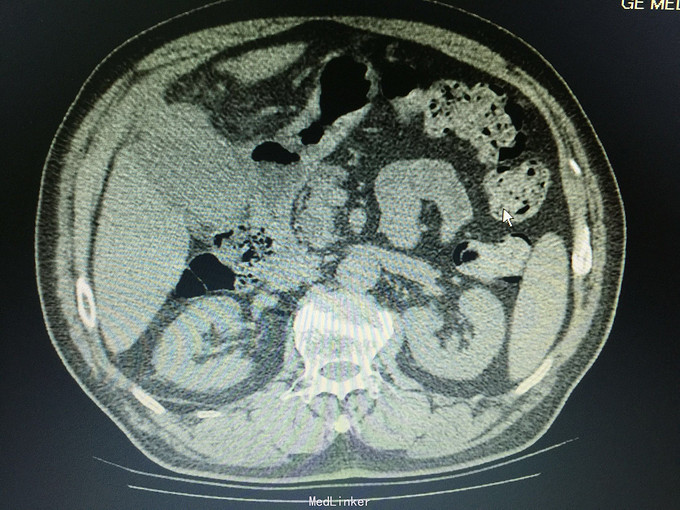

男,74岁 主诉:反复右上腹疼痛10年,再发并加重一天, 现病史:10年前开始反复右上腹疼痛,持续性绞痛,向同侧肩背部放散,曾经在当地医院以“胆囊结石”治疗,效果不佳,10年来反复发作,10小时前再次发作并疼痛难忍,来诊,无发热,无恶心、呕吐,尿色深,大便正常。

痛苦表情,皮肤及巩膜轻度黄染,腹部平坦,右上腹压痛,无肌紧张及反跳痛,未及包块,莫氏症阳性,肝区扣痛明显。 辅助检查:CT:胆囊轮廓欠清晰,密度不均,底部局限性增厚并向内突起,胆囊内见高密度影,胆总管扩张。

诊断:胆囊占位,胆囊结石,胆囊炎 处理:手术治疗,术中见大网膜与腹膜广泛粘连,胆囊质硬,与肝脏、12指肠及横结肠广泛粘连,与胃小弯及幽门部侵润致密。行胆囊癌根治术,胃破裂修补术,胆总管切开T形管引流,腹腔冲洗引流术。病理证实为胆囊中分化腺癌侵及浆膜层。(胆囊及胆总管内未见结石)